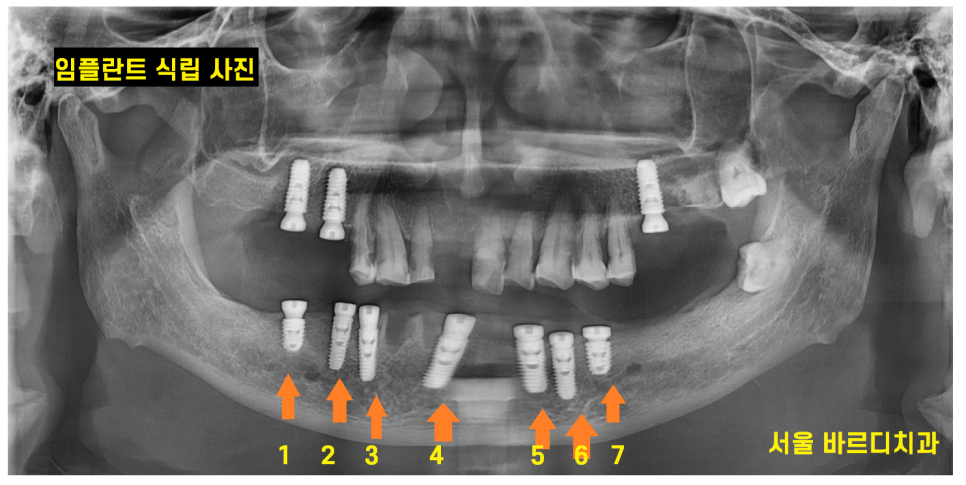

240514

수술은 하루에 전악 심는 것으로 진행되었습니다.

환자분이 근무를 하시다보니 시간 나는 날이 들쭉날쭉이고

언제 다시 외국으로 가실지 몰랐기 때문에

네비게이션 임플란트로 가이드를 미리 제작

하악 전체 임플란트와

상악은 3개 수술을 완료하였습니다.

240808

하악 전체 임플란트 치료였기에 높이를 재건해주는게 중요했습니다.

임시치아 과정도 거치고

어금니 부터 제작하여 높이를 복구해준 뒤

아래 앞니 보철을 맨 마지막으로 제작해드렸습니다.

241025

치료 후 사진입니다.

하악 전체 임플란트 7개로 12개의 머리를 완성

상악도 3개의 임플란트 치료를 진행했습니다.

약 5개월정도 치료 기간이 걸렸습니다.